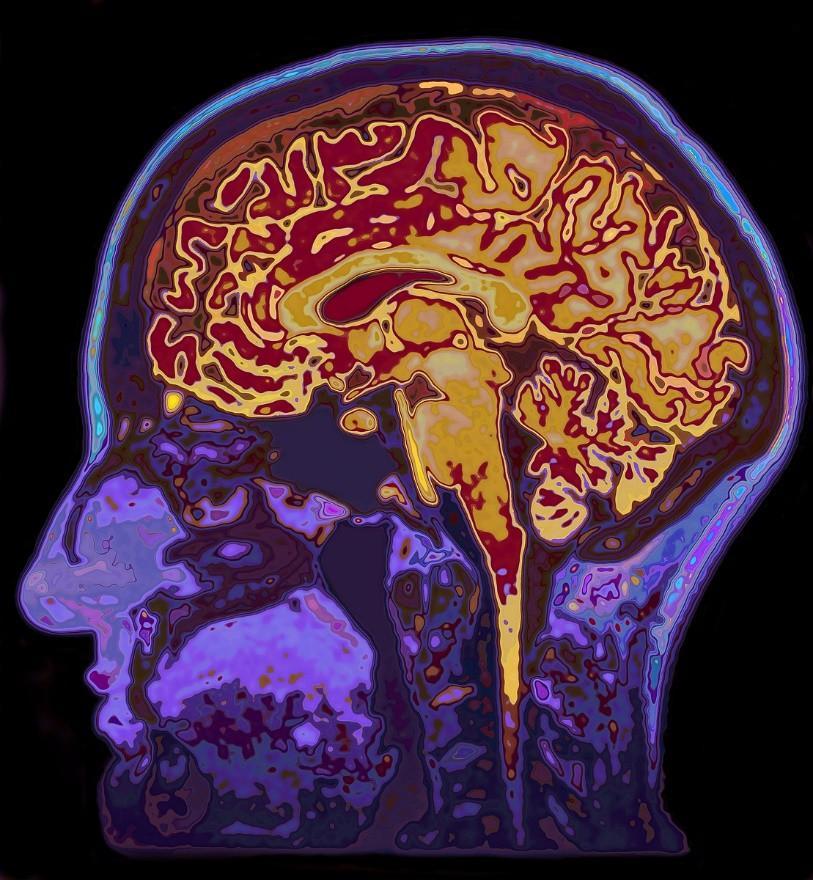

頭部MRI圖像 (圖片來源:Veer圖庫)

然而,大腦細胞數量巨大,猶如浩瀚的星空般讓人望而生畏。在如此龐大的細胞羣體中尋找特異性細胞,就如同在茫茫大海中尋找特定的沙粒,其難度可想而知。每一類細胞都有着獨特的形態、特性和功能,要從這數以億計的細胞中準確地識別出人特異性的細胞,更是一項艱鉅的挑戰。不僅需要先進的技術手段,還需要耗費大量的時間和精力進行數據分析,因此,鑑定人腦中特異性細胞及其功能是一個艱難的挑戰。